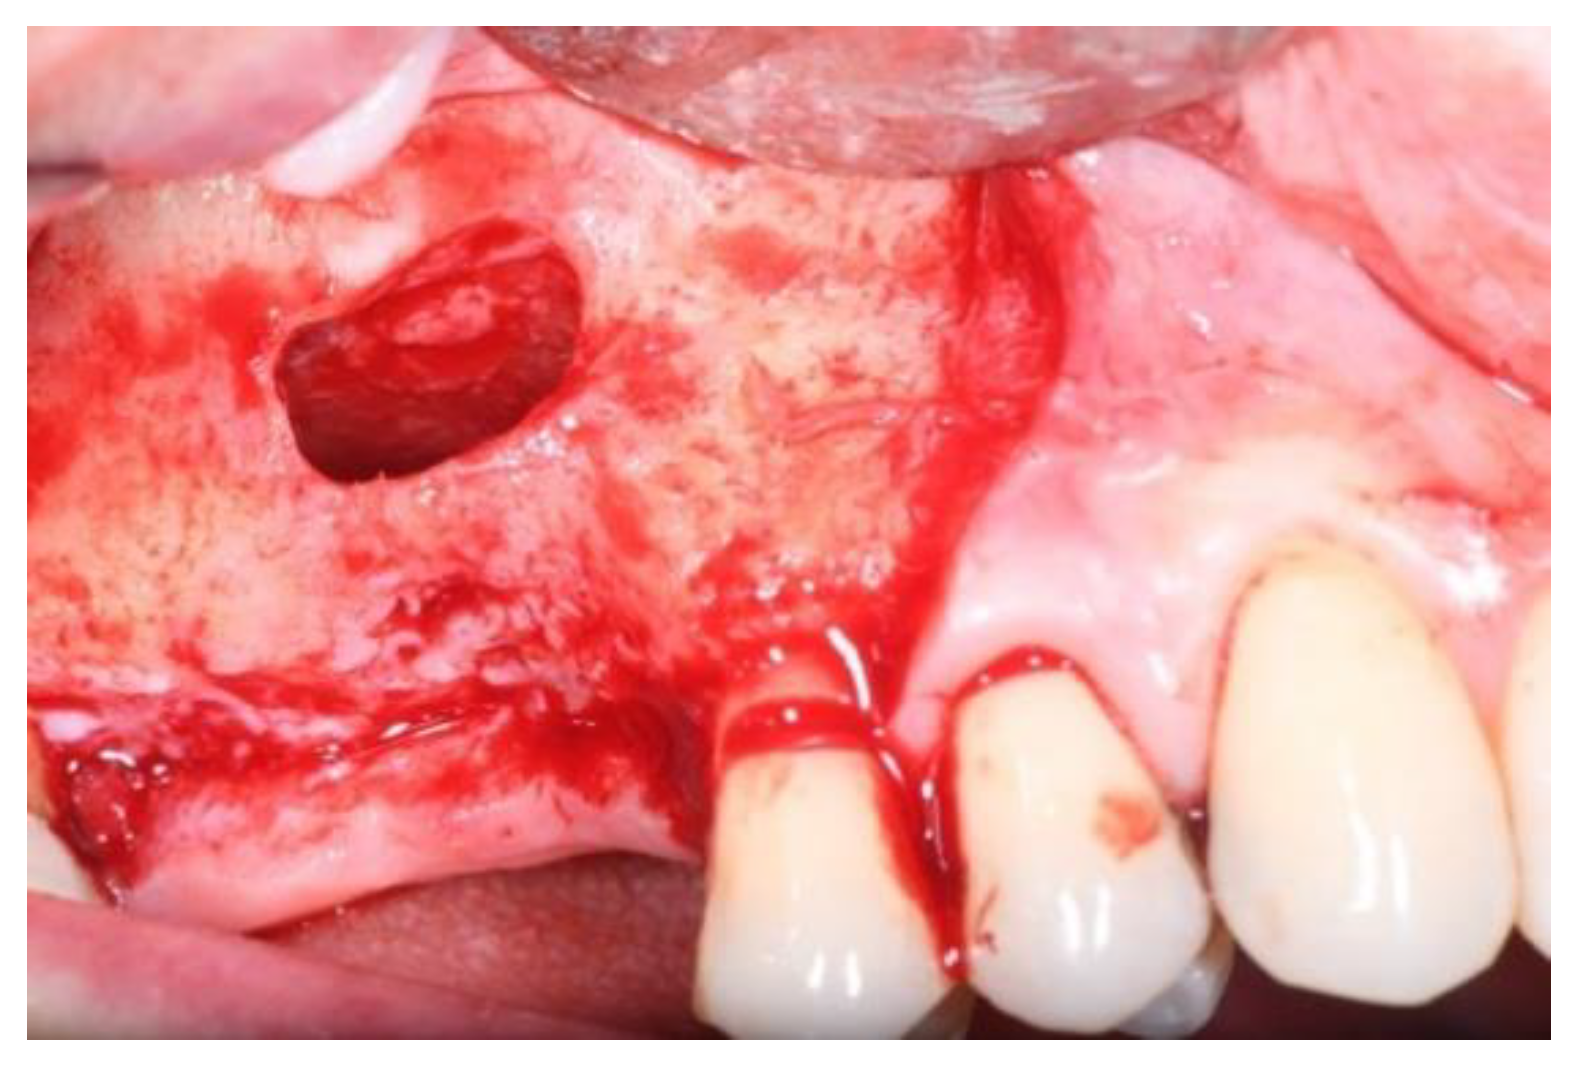

2. Materials and Methods

2.1. Surgical Procedures